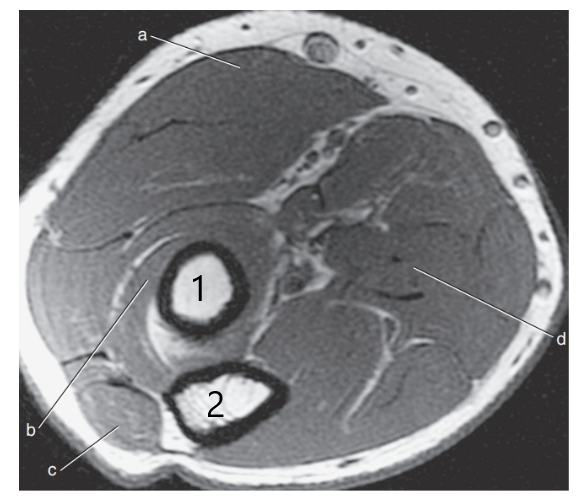

What is letter a?

Median nerve

What anatomy is # 1 ?

Humeral head

What anatomy is # 2 ?

Scapula